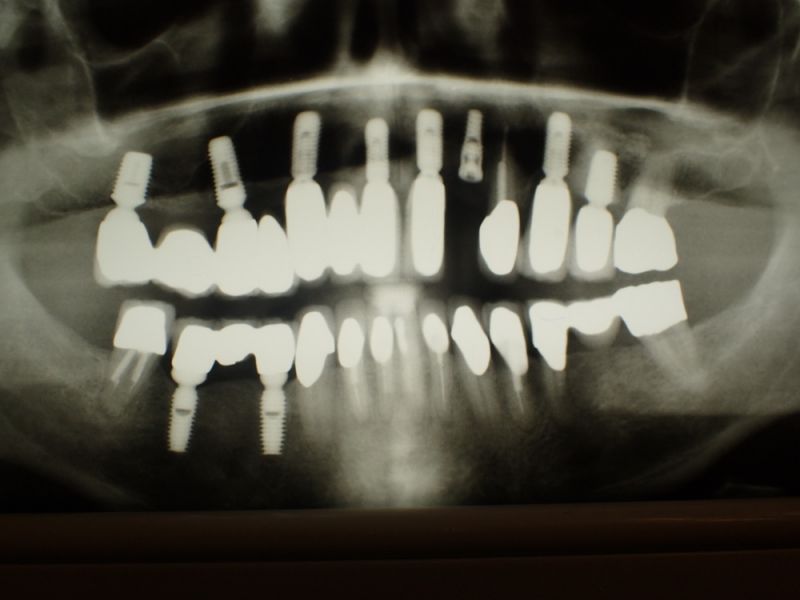

Kieler Patient erhält implantatgestützte Kronenversorgung 22

Dieser Patient ist gesetzlich krankenversichert und hat sich nach und nach inzwischen im CMD CENTREUM KIEL 10 Implantat inserieren lassen.

In diesem Fall wäre es sogar möglich gewesen auf das neue Implantat 22 zu verzichten und eine Versorgung auf den vorhandenen Implantaten zu begründen.

Das hätte aber zu einem wesentlich höheren wirtschaftlichen Aufwand geführt, weil die dann notwendige Prothetik, die von den Implantaten hätte entfernt und nachfolgend wieder neu hätte erstellt werden müssen, wesentlich teurer gekommen wäre, als ein neues Implantat mit einer neuen Krone darauf.